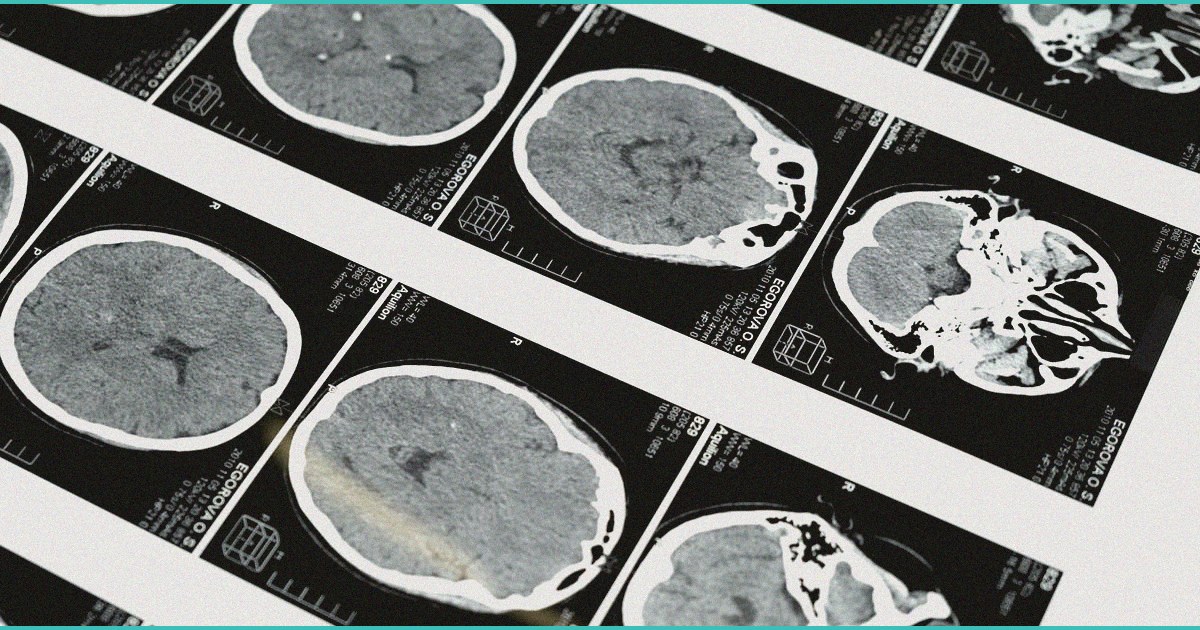

brain scans reveal how a woman voluntarily enters

Brain scans reveal how a woman voluntarily enters a psychedelic-like trance without drugs